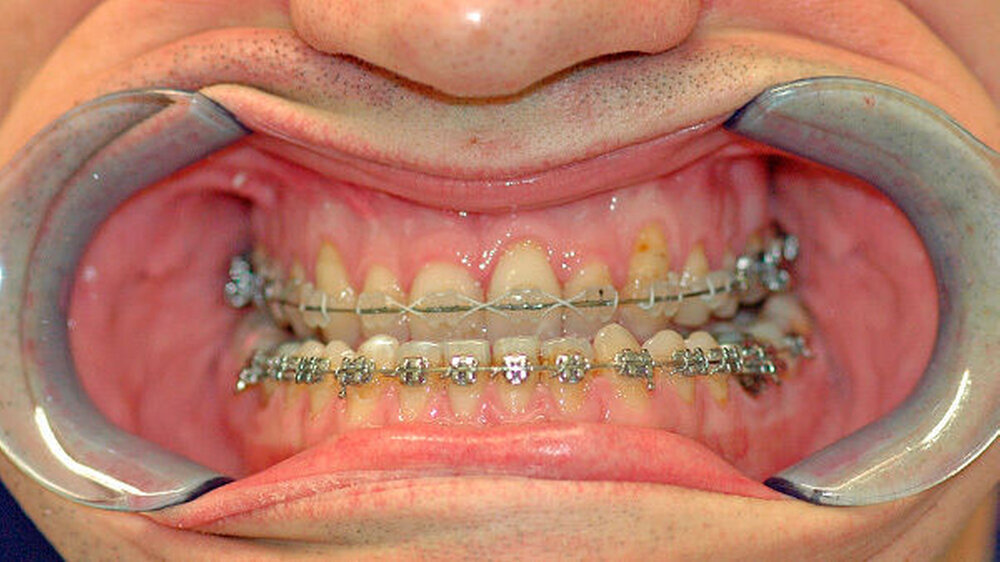

Das deutlich harmonischeres Profil drei Monate nach der Operation: Im Mai des nachfolgenden Jahres wurden die Metallplatten in einem ambulanten Eingriff wieder entfernt. Eine Multibandapparatur hält die Zähne noch "in der Reihe". Der Patient kann heute dank der individuellen innovativen Behandlung ein normales Leben führen, die Gesichtsästhetik und seine Kaufunktion sind vollständig wiederhergestellt.